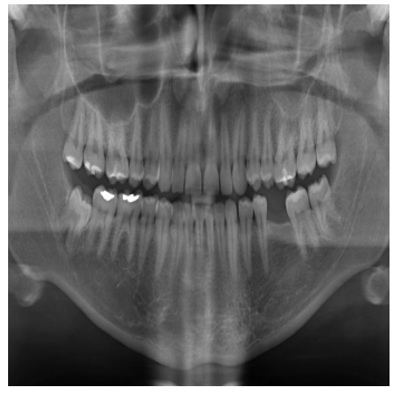

However, manual interpretation has significant areas for improvement: it is time-consuming, susceptible to human error, and highly reliant on the clinician’s competence. Separating and identifying various components of dental structures, including teeth, roots, and adjacent tissues, within medical images (e.g., X-rays, MRI, and CT scans), is one of the most critical areas of focus in dental imaging. According to Zhang et al.[6], segmentation divides an image into meaningful regions corresponding to anatomical features. It is increasingly necessary to implement automatic and precise segmentation of dental images. The underpinning of this urgency is an abundance of variables. Manual interpretation may be subjective initially; in equivocal situations, two specialists may not consistently agree on the exact diagnosis or treatment approach. As illustrated in Figure 1(b), the complex character of dental structures and the proximity of tangible elements, such as teeth and jawbones, present substantial obstacles. Finally, human eyes are impaired in their ability to differentiate between teeth in dental X-rays due to the frequent overlap of teeth, as illustrated in Figure 1(a). Identifying the fine details of dental roots and cavities may prove challenging in low-resolution images. The existence of these obstacles underscores the urgent need to automate these procedures with more resilient, precise, and scalable methodologies.

Figure 1: (a) shows the overlapped teeth, and (b) denotes the sharpness of teeth in different shapes.